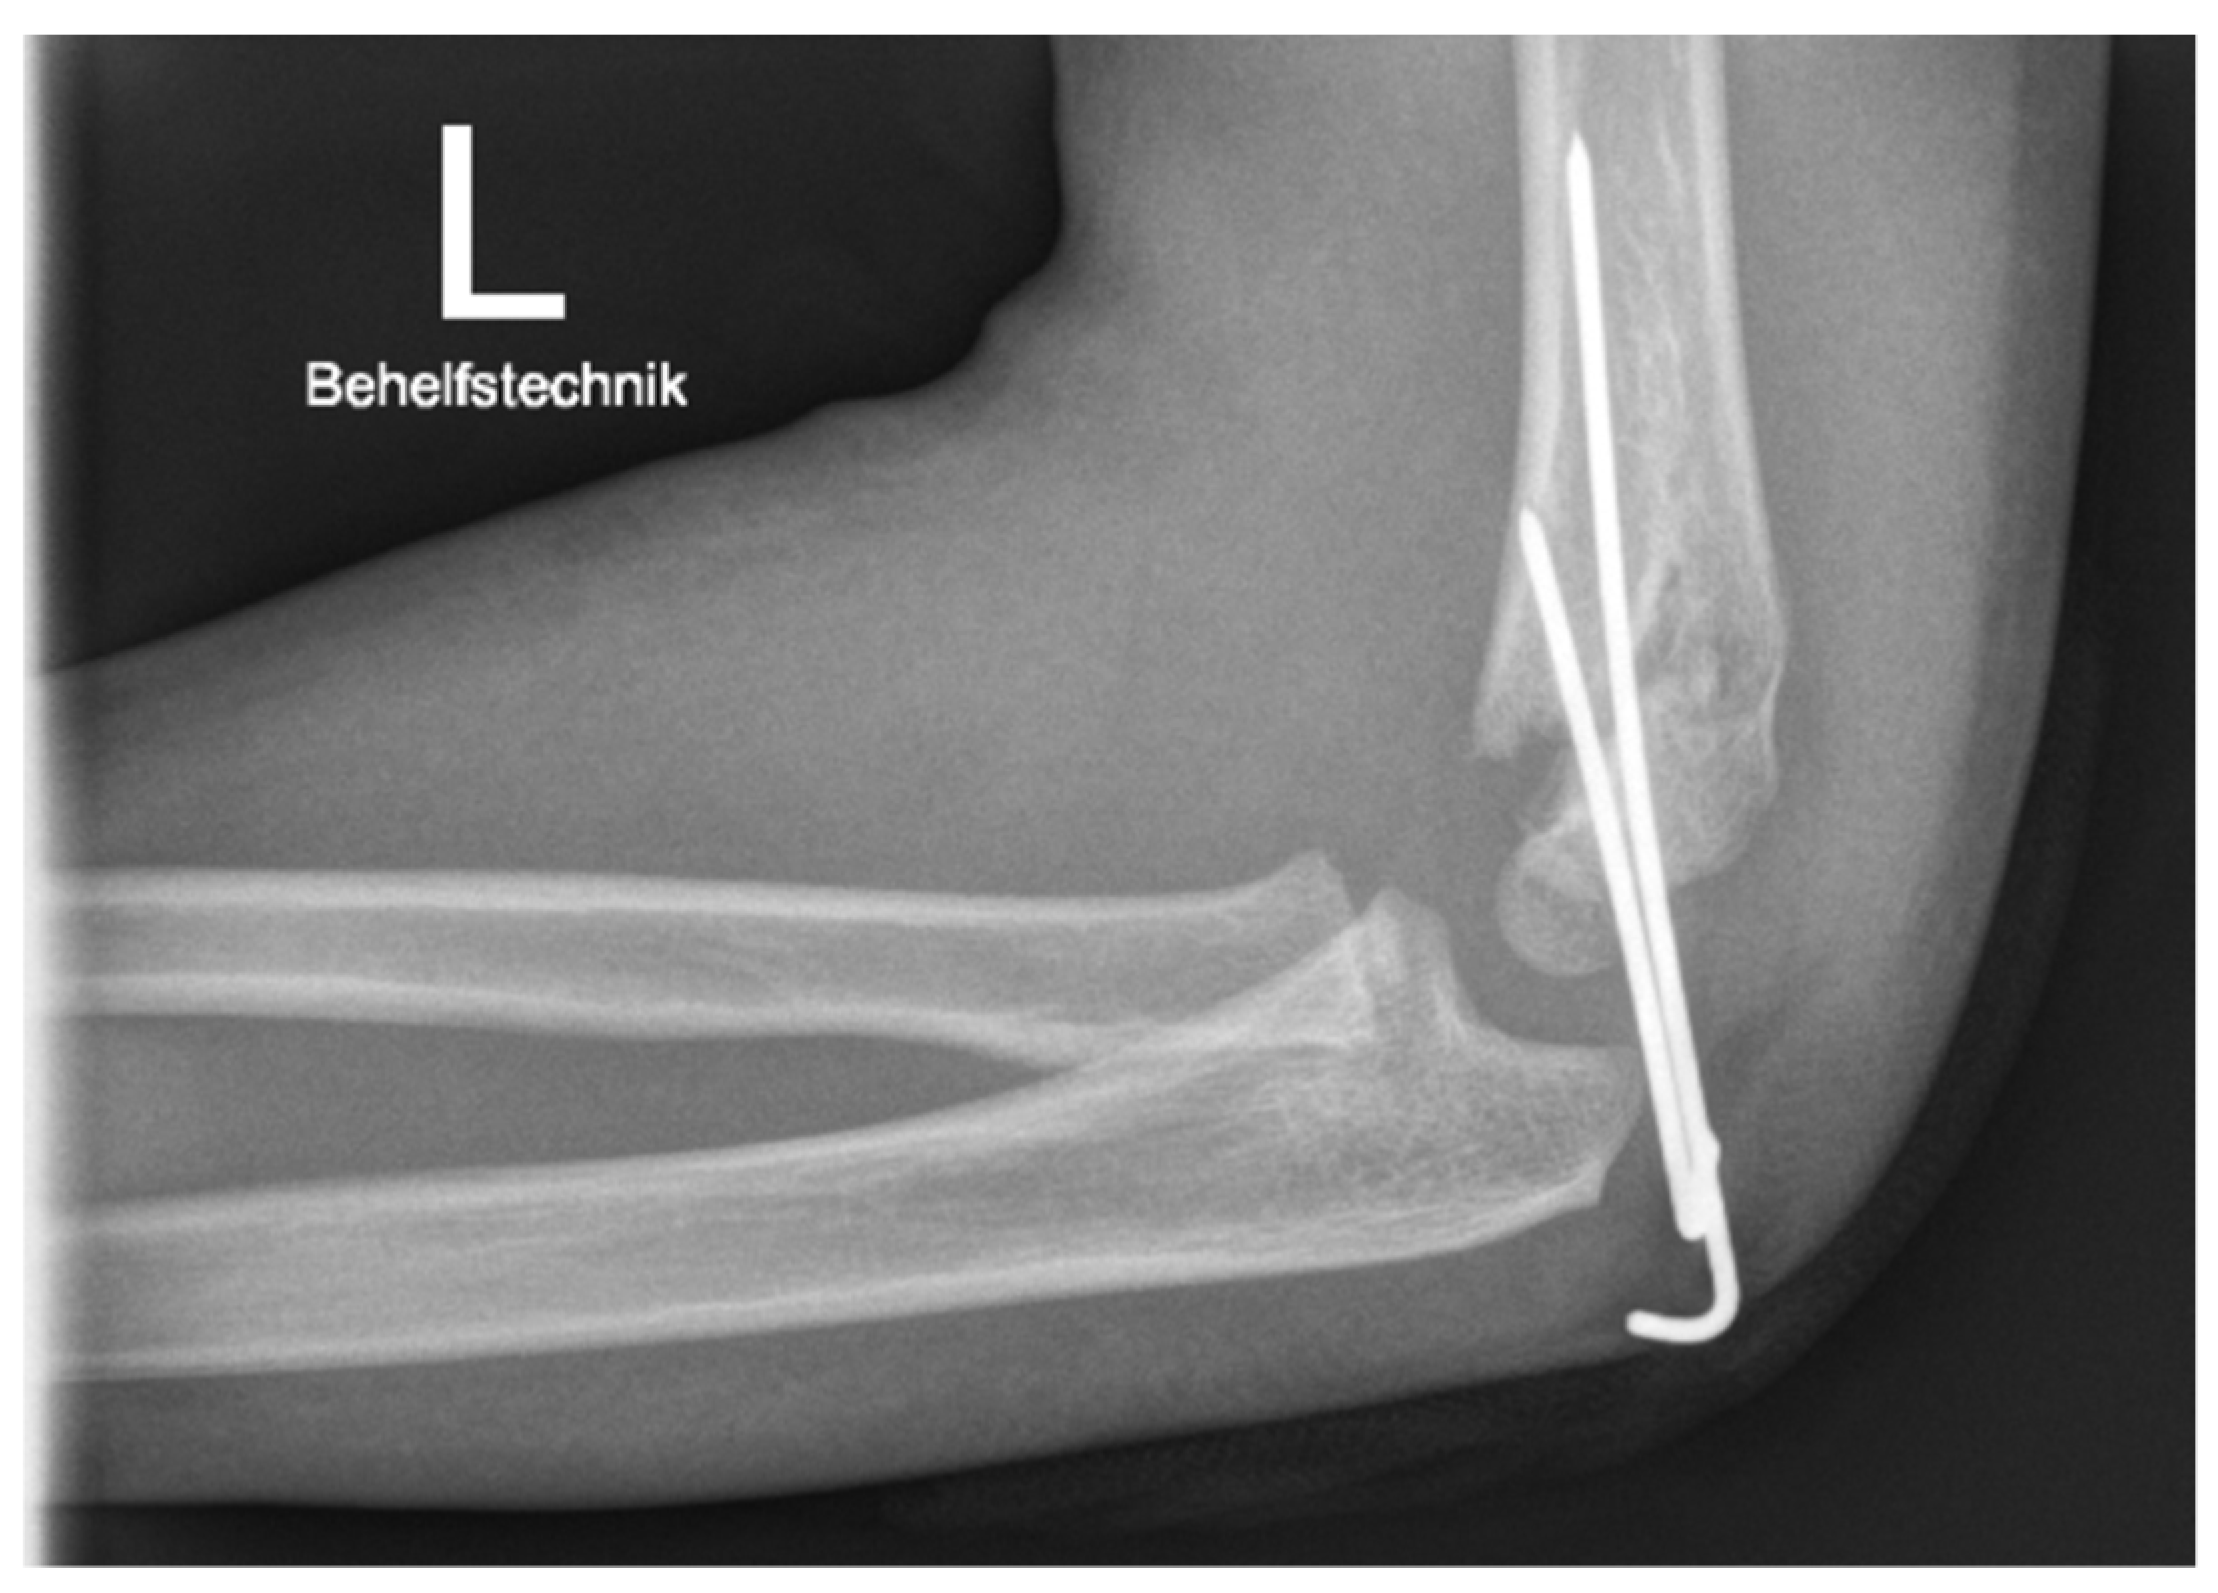

| Surgery | 14 (36%) PCP | 25 (64%) AN |

| Surgery | 3 (25%) PCP | 9 (75%) AN |